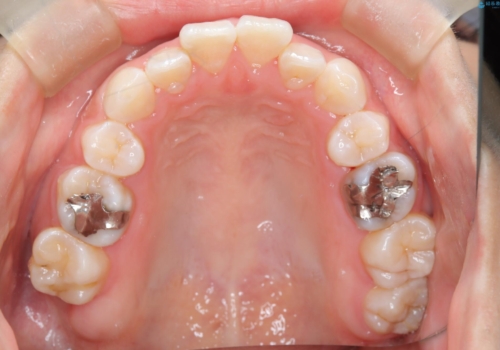

- 子供のころに矯正治療をされていたが、後戻りをしてしまったという20代女性の患者様です。上顎左右の2番が、咬合時に下顎の歯よりも内側に入っているクロスバイトという状態でした。奥歯の咬合関係は変えずに、マウスピース矯正にて前歯の並びを綺麗なアーチに仕上げました。再度後戻りしてしまうリスクを軽減させるために、リテーナー(保定装置)をお渡ししています。